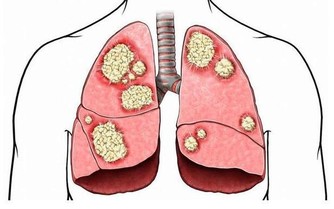

增強抵抗力、加速創傷恢復、防治心血管疾病、

降血糖、降血壓、降膽固醇、改善心血管病、

治療風熱感冒、防治腎結石、袪痰、補鈣、

治療風濕病、懷孕止吐、婦科疾病、退燒。